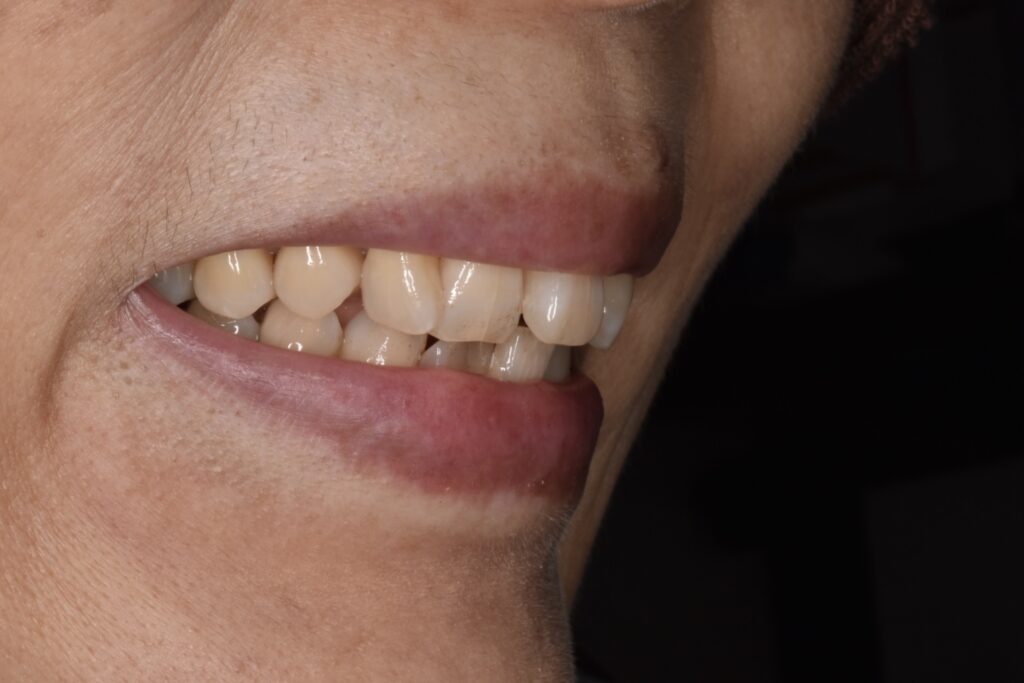

矯正前

前歯を中心に叢生(ガタガタ歯並び)がみられます。

矯正前の横顔や正面、咬合面の写真です。